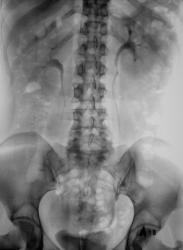

Почки контурируются в типичном месте, обычной формы и размеры. R-позитивных уроконкрементов в проекции мочевыносящих путей на обзорной урограмме не выявлено. ЧЛС контрастированы синхронно, не расширены. Мочеточники контрастированы, левый просматривается на всем протяжении, в нижней 1/3 незначительно стойко расширен, оттеснен кверху и вправо (хотя возможен такой вариант расположения устьев мочеточников - к сожалению правый мочеточник не визуализируется т.е. несчем сравнить). В мочевом пузыре, слева от срединной линии, дефект наполнения с четкой неровной границей.

Всё же подготовка удовлетворительная и качество снимков хорошее, ЧЛС четко видно, при болевом синдроме у пациента не приходиться настаивать на идеальную подготовку, всё равно минимально но перистальтика снижена бывает, а мед.сестры ещё вгоняют помимо воды ещё и газ в кишечник, поэтому часто так и получается. При возможности если пациент ни тучный, то я обычно, при экстренности, беру без подготовки, обычно цифра помогает в этом деле отлично.